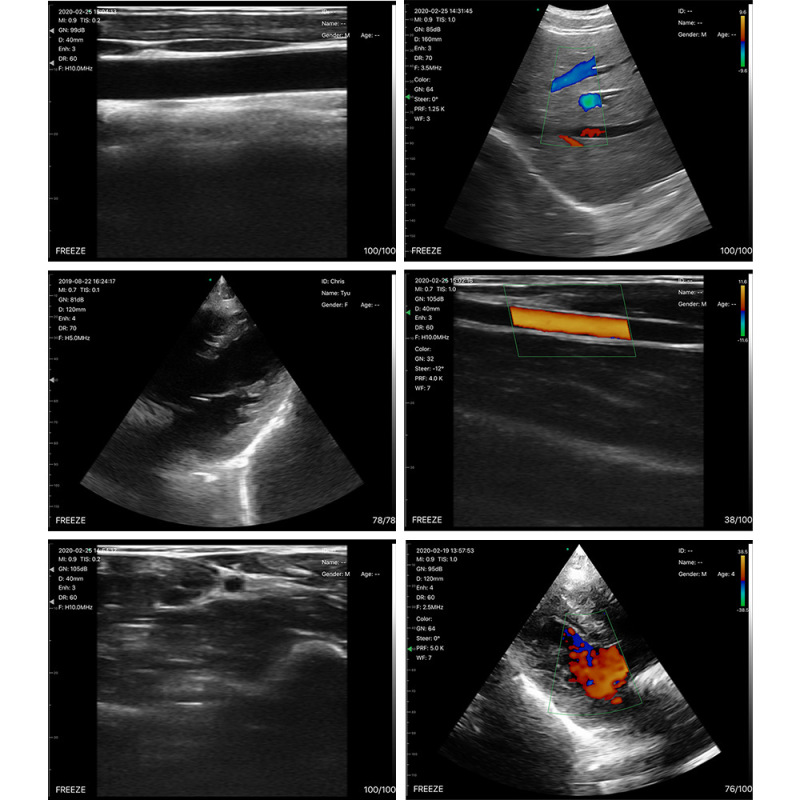

外国貿易専用ハンドヘルドハンドヘルド B 超音波マシン小型ポータブル人間および獣医 B 超音波ワイヤレス高周波リニア超音波

商品詳細